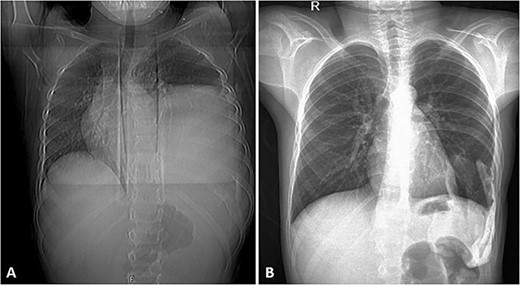

His postoperative course was uneventful. A chest CT was performed following the surgery, and the results revealed that the previous left lung mass had been completely removed without definite residue (Fig. 4). The patient is on close follow-up monthly with a physical exam, chest X-ray, and chest CT every 3–6 months. For the past two years, there have been no discernible clinical or radiological indicators of recurrence (Fig. 5).

Selected axial cuts of the patient’s chest–lung window. The previously mentioned left posterior chest wall mass is no longer seen with post-operative changes noted.